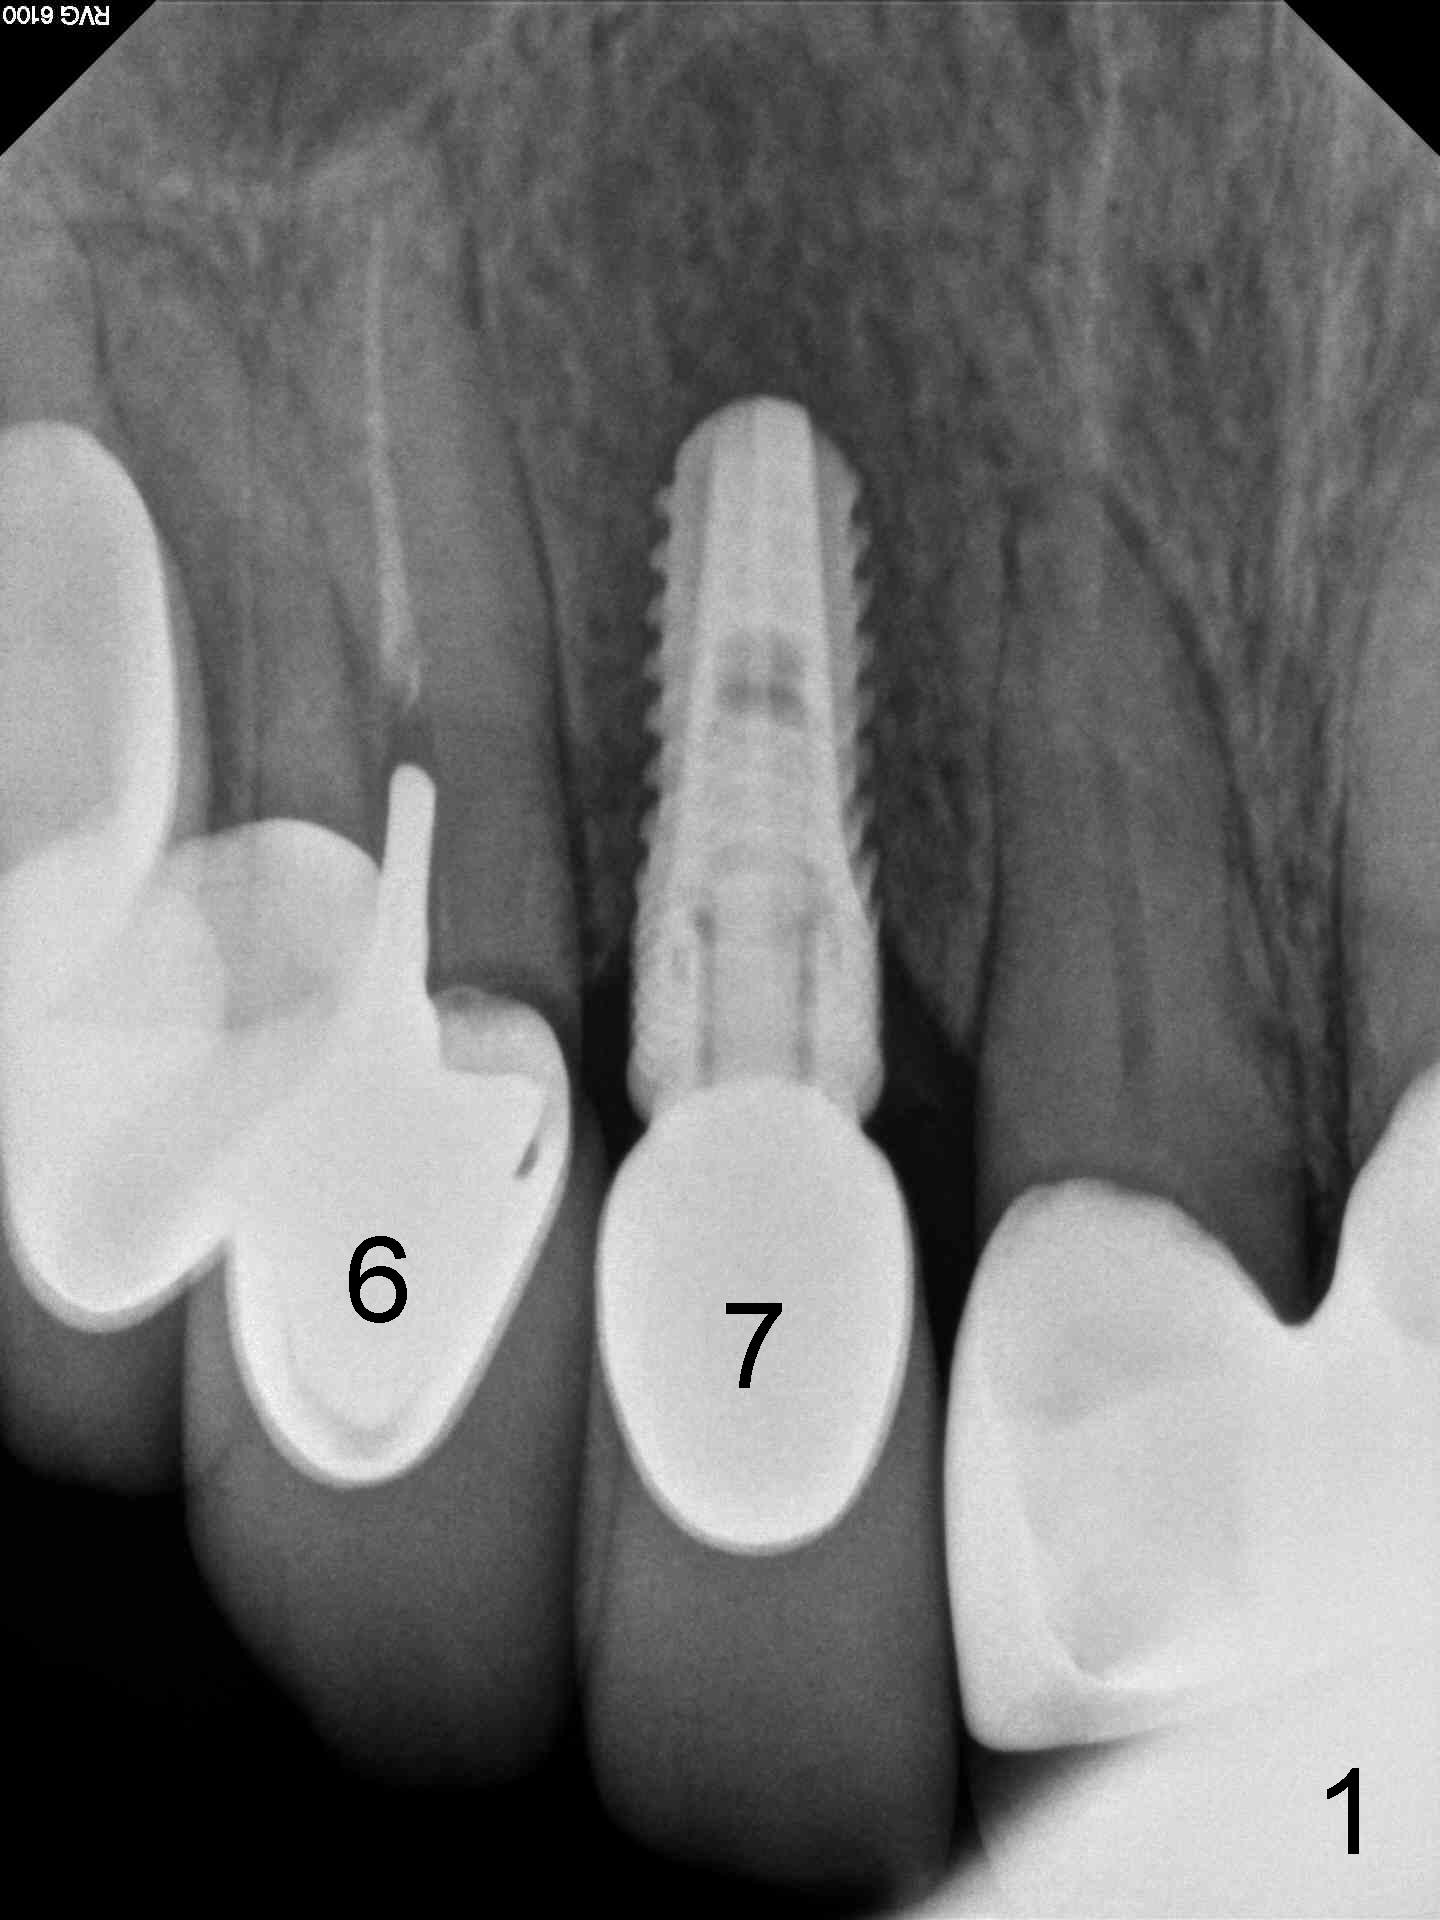

CBCT studies reveal that the implant perforates the buccal plate at the site of #7 and that there is still enough bone to support 3.0x17 mm one piece implant (Fig.2,3).  There is limited bone apical to the tooth #6.  The implant should be at least 17 mm for bone level and 14 mm for tissue level (Fig.4) or preferably 20 mm with sinus lift (Fig.5).  The diameter will be 4.5 mm (Fig.6) or 5 mm (Fig.4.5).